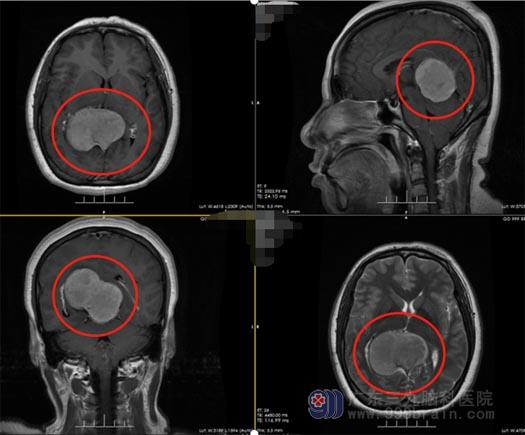

入院后,神经外五科医生团队马上给李阿姨安排了一系列的检查,CT血管成像(半球脑动脉)检查意见:松果体区占位性病变,血供丰富,边缘多发小血管影缠绕,邻近大脑深静脉及直窦受压、移位,可见明显增粗的直窦迁曲主要汇入右侧横窦,部分仍汇入窦汇;余颅脑CTA及CTV未见明显异常;建议MRI检查;3.0TMF颅脑平扫,检查意见:1.小脑幕上松果体区占位性病变,考虑脑膜瘤可能性大,相应小脑扁桃体稍变尖、下移;2.部分性空蝶鞍;3.双侧上颌案、筛案少许炎症;鼻咽部软组织稍增厚。